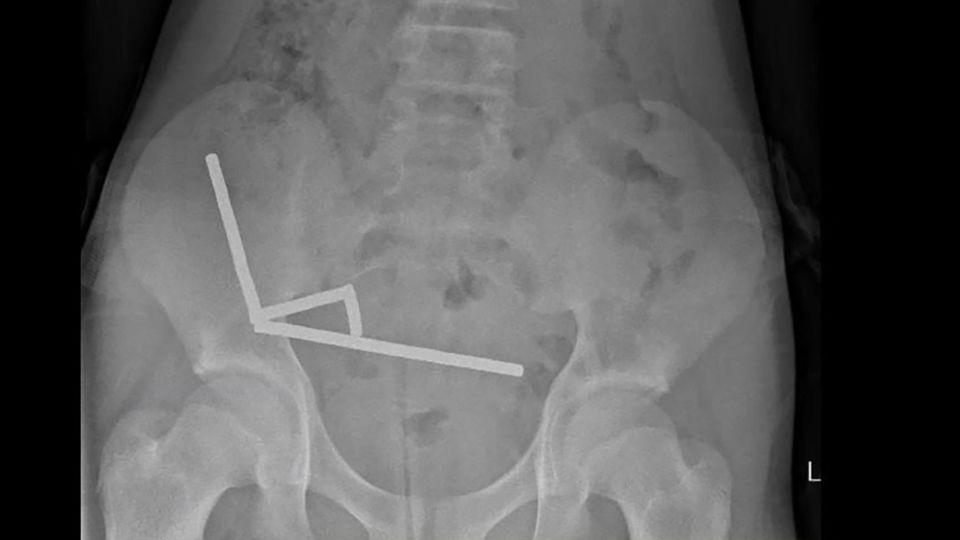

El párvulo, cuya identidad no fue revelada, comió entre 80 y 100 imanes de neodimio, cada uno de cinco milímetros por dos milímetros de tamaño, según el crónica.

Los imanes de suscripción potencia, que a menudo se venden como juguetes de escritorio para adultos, son pequeños pero peligrosos si se ingieren. Su cachas afecto magnética puede hacer que partes del tracto digestivo se peguen, lo que provoca complicaciones graves como necrosis por presión, hoyo o infecciones potencialmente mortales, según el crónica. A menudo se requiere cirugía,